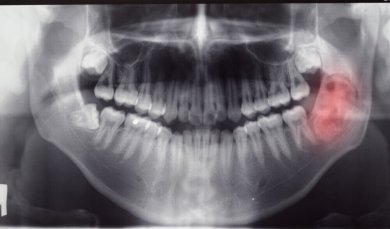

Diagnóstico de tumores e cistos mandibulares

Na maioria das vezes, os tumores e cistos não provocam sintomas e a descoberta é acidental. No entanto, em alguns casos, podem surgir sintomas como dor nos dentes, inflamação, dor local e abaulamento da gengiva.

Para obter o máximo de informações sobre possíveis tumores e cistos mandibulares, serão solicitados exames de diagnóstico, como radiografias, ressonâncias ou ortopantomografia.

Além disso, uma biópsia pode ser realizada para remover uma amostra das células do tumor ou cisto para análise. Com essas informações, o médico vai propor o tratamento apropriado para tratar o tumor ou cisto da maneira mais eficaz possível.